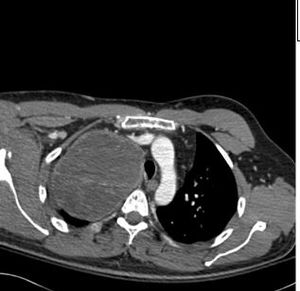

The mediastinal benign schwannomas is a nerve sheath tumor composed of Schwann cells. These tumors are often asymptomatic and found incidentally.

Two weeks after injury to the right chest wall and shoulder, the patient continues to have pain. He also reports numbness and tingling in his hands bilaterally. What do the ED images reveal?